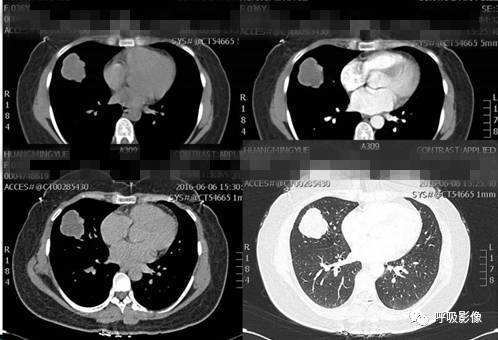

案例二:

简单病史:女,43岁。咯血10余天。既往有子宫肌瘤切除病史。于山东省肿瘤医院查体,CT示:1.右侧附件区囊实性占位,同侧卵巢静脉显著增粗,考虑恶性肿瘤。2.双肺结节,考虑转移。3.宫体低密度灶,不除外子宫肌瘤。4.腹部、颈部扫描未见异常。子宫肌瘤病理切片会诊:子宫平滑肌瘤。盆腔附件包块穿刺活检细胞学检查示:查到可疑癌细胞。组织病理示:查见极少肿瘤细胞,考虑癌细胞。行紫杉醇联合卡铂化疗一疗程。

诊断: 绒毛膜癌肺转移。

诊断依据: 中年女性,有咯血病史。既往有子宫肌瘤切除病史。CT示右侧附件区囊实性占位,同侧卵巢静脉显著增粗,考虑恶性肿瘤。盆腔附件包块穿刺活检细胞学检查查到可疑癌细胞。病理示查见极少肿瘤细胞,考虑癌细胞。

胸部CT示双肺多发结节影,强化明显,内见明显坏死,提示血供丰富。

转移瘤多具有原发肿瘤特点,本例转移瘤为生殖源性肿瘤,盆腔附件包块穿刺活检细胞学检病理均查见恶性肿瘤细胞,结合转移灶坏死、强化明显,需考虑绒毛膜癌缠医可能。

胸部CT双肺多发结节影,强化明显,内见明显坏死,提示血供丰富,这是诊断关键。

治疗结果: 更改化疗方案为DDP 40mg d1-3,BLM 15mg d1-4,VP-16 0.1 d1-5。化疗过程顺利。化疗3次后血HCG降至正常,继续化疗2疗程,血人绒毛膜促性腺激素:0.411 mIU/mL;B超示宫体前壁实质内见3.2*2.0cm高回声肿物,内探及丰富血流信号;胸部肿瘤消退明显。

行全子宫+双附件切除术,术后病理为子宫肌层内片状坏死伴纤维组织增生,炎细胞浸润,未见残留瘤细胞,符合化疗后改变。左右宫旁未见病变。增殖期子宫内膜。宫颈慢性炎。左右卵巢、输卵管组织。15天后复查人绒毛膜促性腺激素<0.100 mIU/mL,胸片检查示双肺转移瘤治疗后消失。化疗1疗程,方案为DDP40mg d1-3,BLM 15mg d1-4,VP-16 0.1 d1-5。